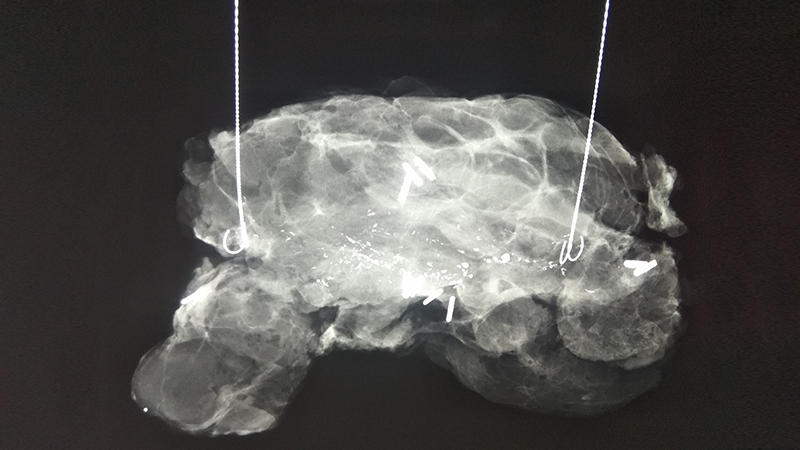

Αφαίρεση αποτιτανώσεων (ασβεστώσεων) μαστού